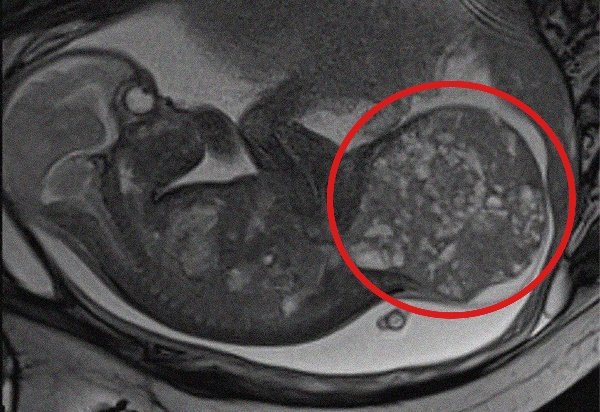

La grande massa rimossa, un teratoma sacro-coccigeo, è una rara neoplasia che si sviluppa nella parte terminale della colonna vertebrale e colpisce circa 1 neonato ogni 35.000-40.000 nati vivi. Pur essendo solitamente benigna, può comportare gravi complicanze per il feto. Tra queste il rischio di scompenso cardiaco, idrope fetale e morte intrauterina.

Nel caso specifico, alla 28° settimana di gestazione, a seguito di una rapida e improvvisa crescita della massa tumorale, gli specialisti dei due ospedali hanno deciso di intervenire in epoca fetale con una procedura mininvasiva di lasercoagulazione ecoguidata dei vasi sanguigni della massa stessa, eseguita presso il comparto operatorio del San Pietro Fatebenefratelli. Utilizzando un laser a diodi è stato possibile ridurre l’afflusso sanguigno al tumore, rallentandone la crescita e permettendo di prolungare la gravidanza fino alla 30° settimana.

La gestione multidisciplinare è proseguita all’Ospedale Pediatrico Bambino Gesù, dove la mamma ha poi partorito con parto cesareo programmato nell’ambito del ‘Progetto Nascita’ dedicato ai nascituri affetti da gravi patologie congenite. Dopo essere venuta alla luce, la neonata – che prima dell’intervento pesava 1,9 chili – è stata immediatamente operata per rimuovere completamente il teratoma di circa 800 grammi, pari ad oltre la metà del suo peso corporeo effettivo (1,1 kg). L’operazione, della durata di circa 3 ore, ha incluso anche la ricostruzione della regione sacrale.